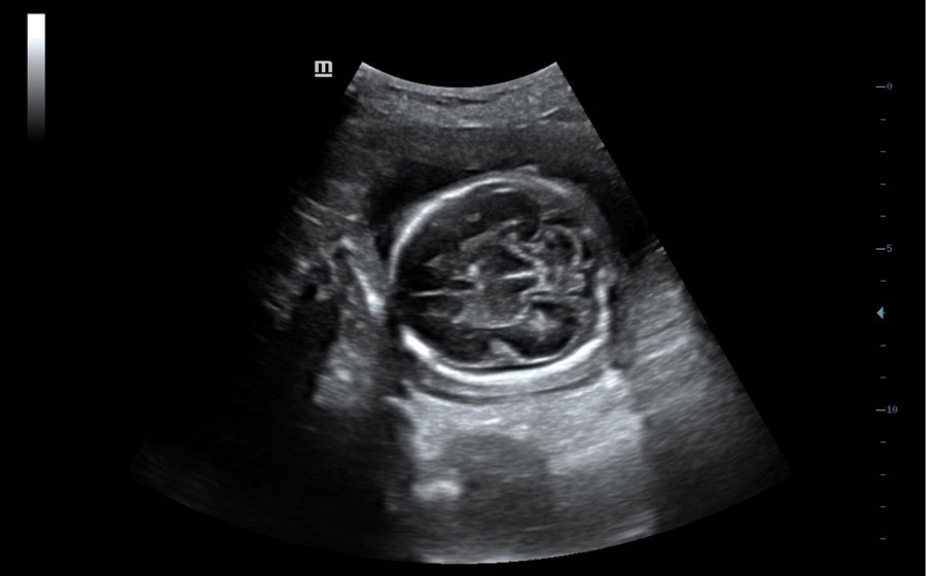

Standaard ultrasoundbeelden

Vergelijking realtimescan ter referentie.